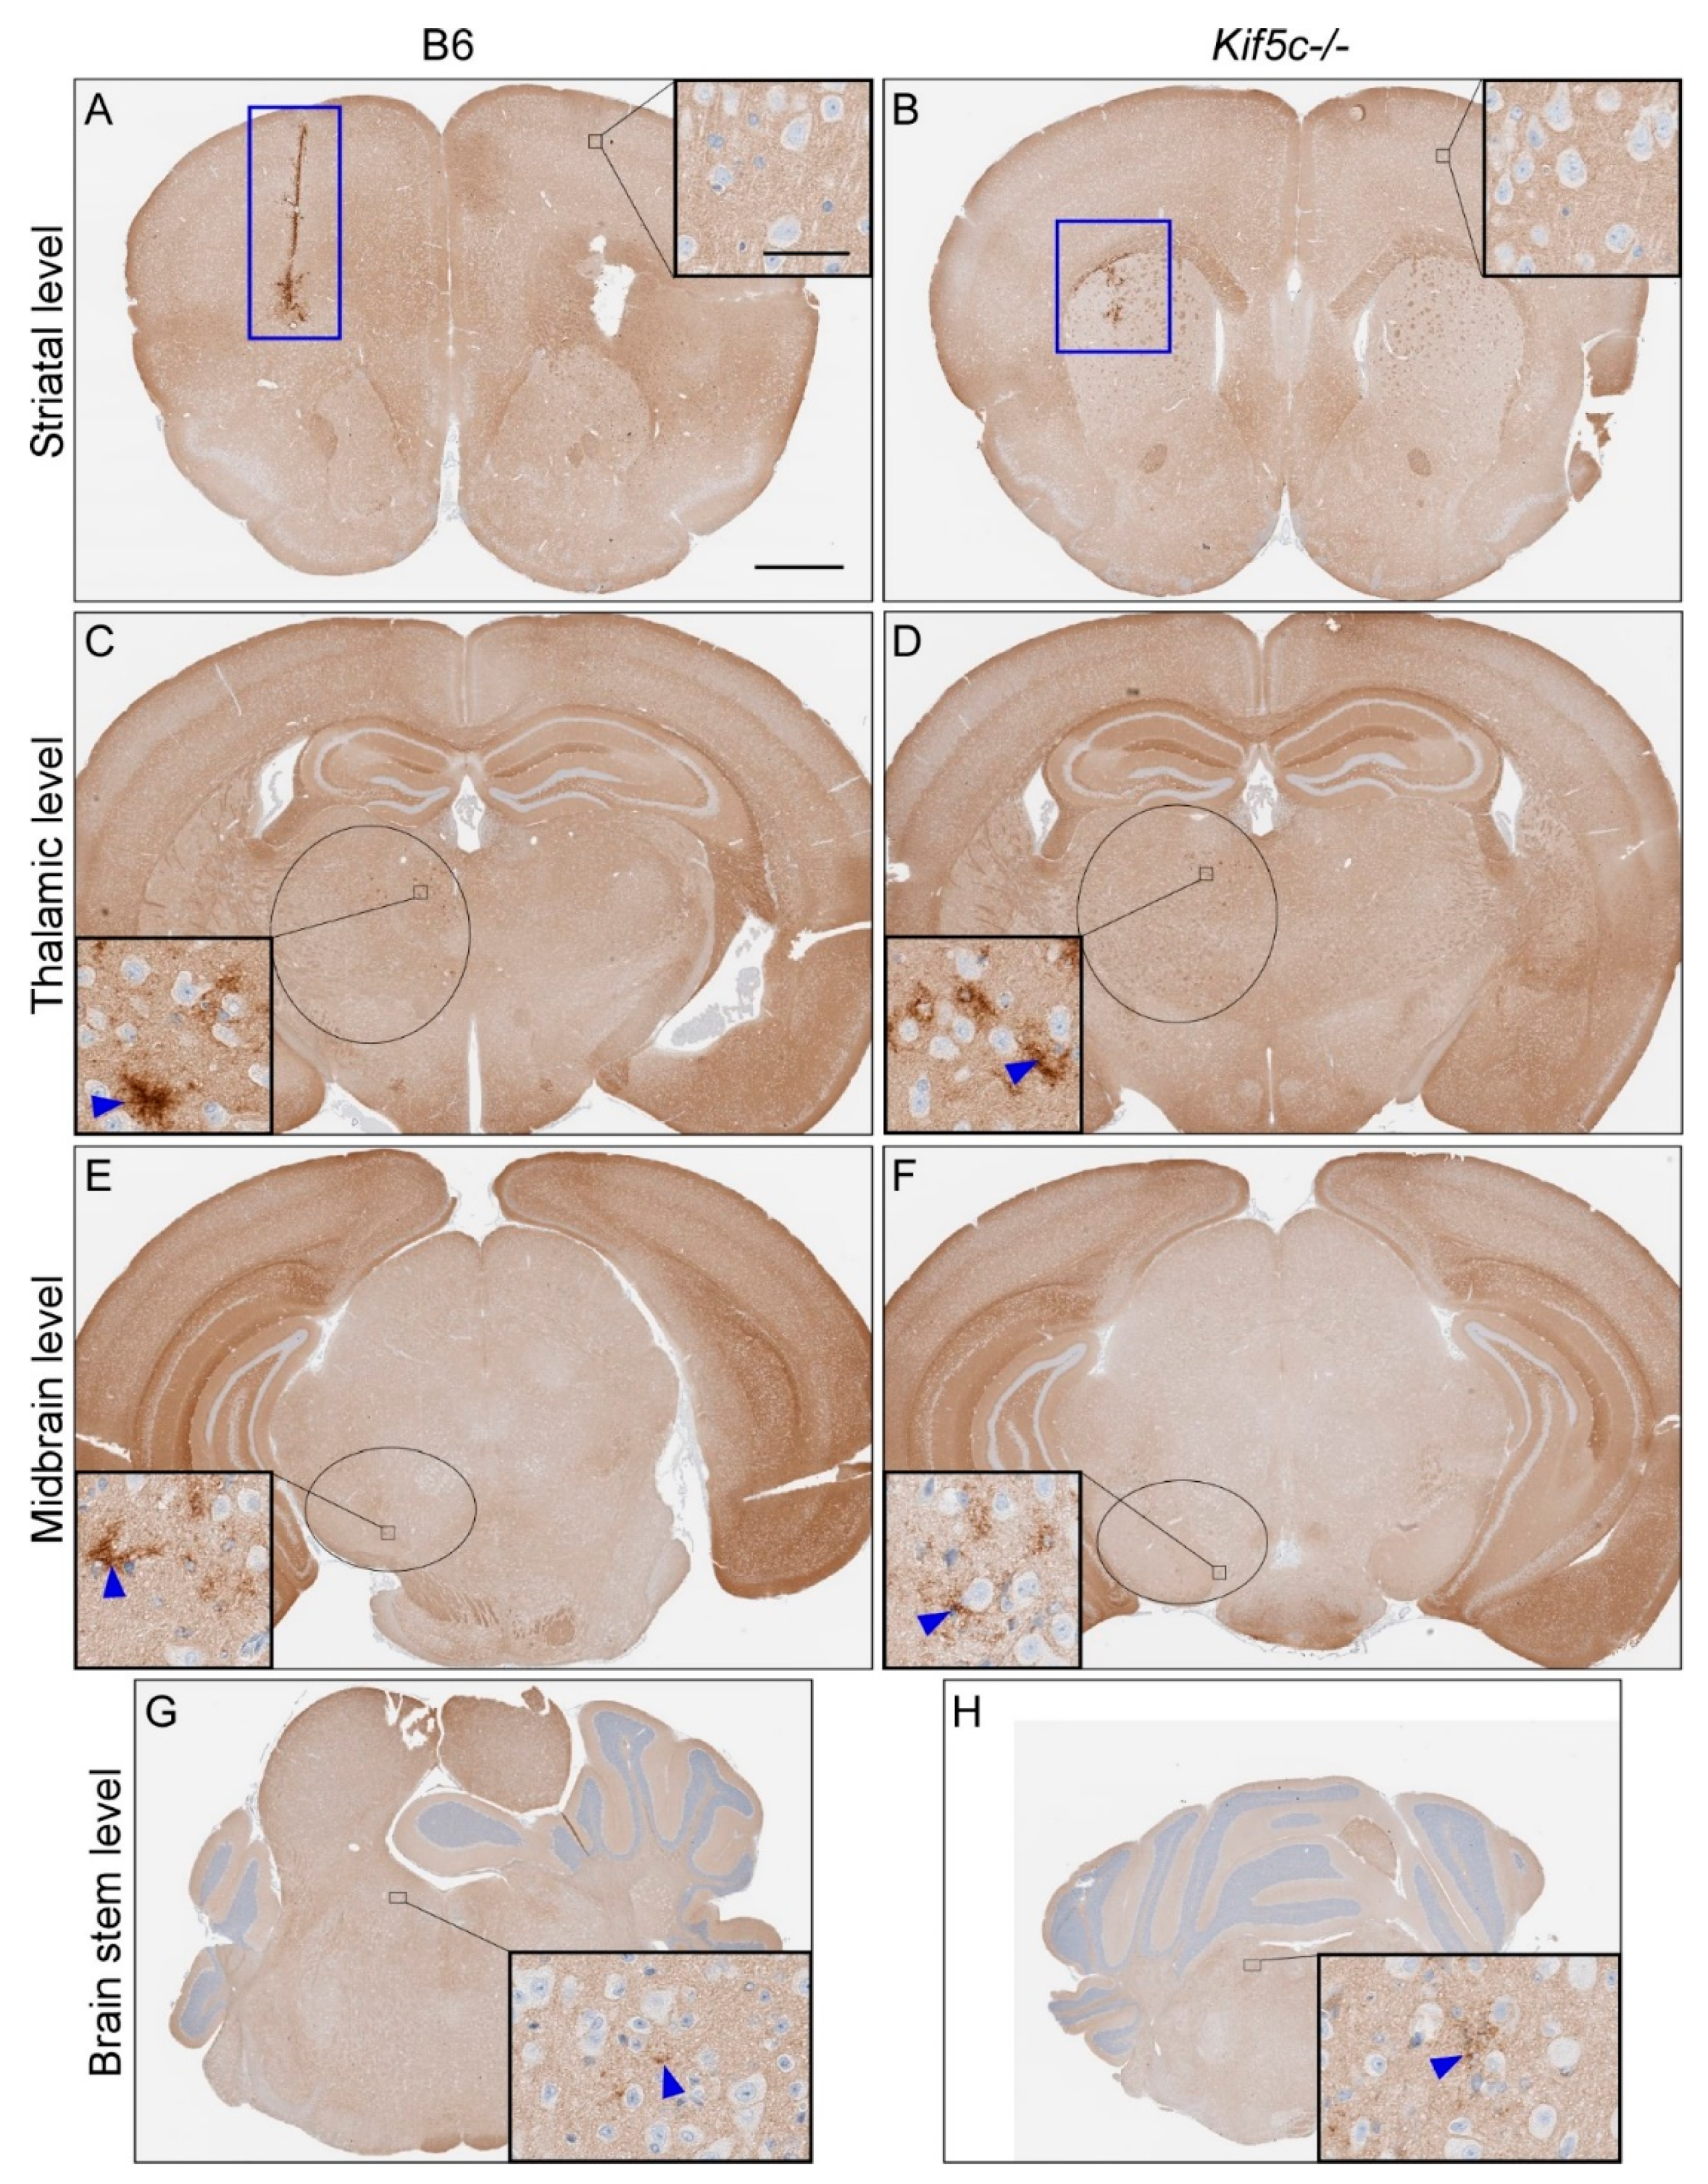

3.1. The 22 L PrPSc Spreading Kinetics in B6 and Kif5c−/− Mice

| Scrapie Strain | Mouse Strain | Time Point (dpi 2) | Brain Region | |||||||||

|---|---|---|---|---|---|---|---|---|---|---|---|---|

| Striatum (0) 1 | Thalamus (3.2) 1 | Midbrain (5) 1 | Rostral Pons (7) 1 | |||||||||

| PrPSc Present 3 | PrPSc Score 4 | PrPSc Present 3 | PrPSc Score 4 | PrPSc Present 3 | PrPSc Score 4 | p-Value 5 | PrPSc Present 3 | PrPSc Score 4 | p-Value 5 | |||

| 22 L | B6 | 7 | 2/2 | 1 | 0/2 | 0 | 0/2 | 0 | 0/2 | 0 | ||

| Kif5c−/− | 7 | 2/2 | 1 | 0/2 | 0 | 0/2 | 0 | 0/2 | 0 | |||

| B6 | 25 | 5/5 | 2 | 5/5 | 1 | 3/5 | 0–1 | 0.46 | 4/5 | 0–1 | >0.99 | |

| Kif5c−/− | 25 | 3/3 | 2 | 3/3 | 1 | 3/3 | 1 | 2/3 | 0–1 | |||

| B6 | 40 | 4/4 | 3 | 4/4 | 2 | 4/4 | 2 | 4/4 | 1 | >0.99 | ||

| Kif5c−/− | 40 | 4/4 | 3 | 4/4 | 2 | 4/4 | 2 | 3/4 | 1 | |||

| B6 | 60 | 3/3 | 2–3 | 3/3 | 3 | 3/3 | 1–2 | 3/3 | 1–2 | |||

| Kif5c−/− | 60 | 3/3 | 3 | 3/3 | 3 | 3/3 | 2 | 3/3 | 1–2 | |||